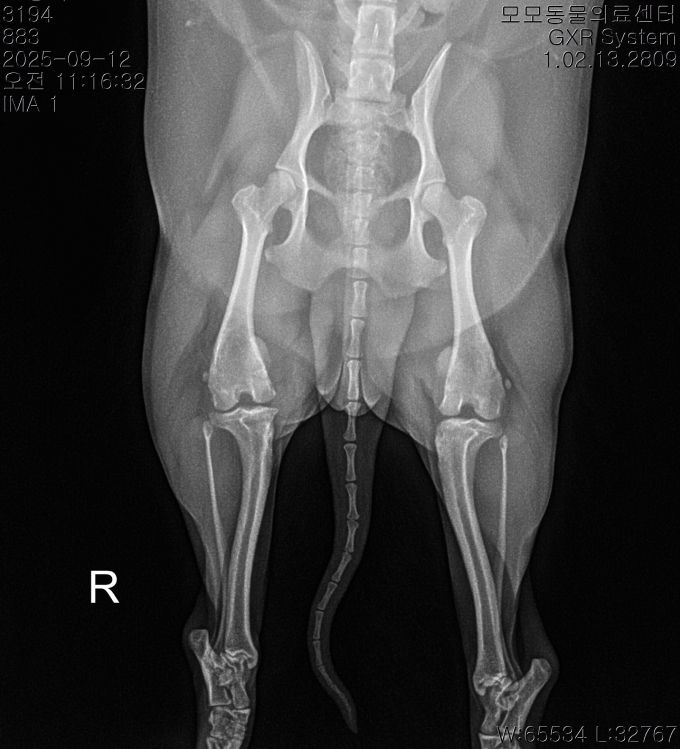

BEFORE

AFTER